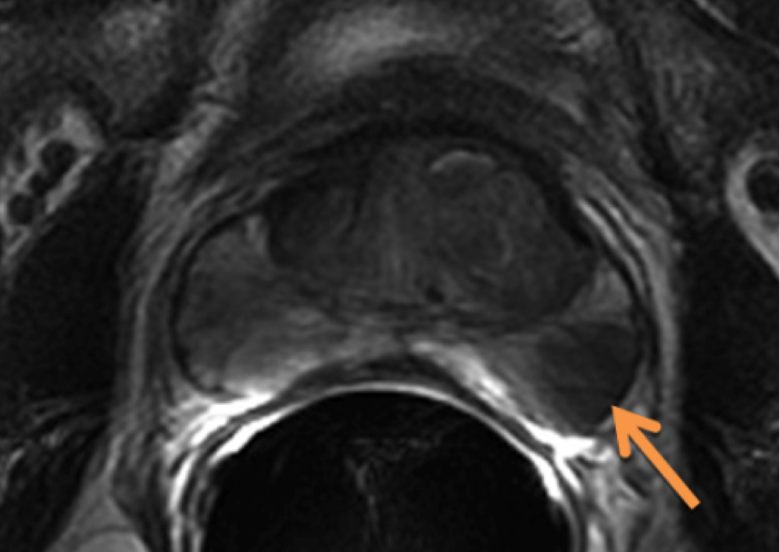

Additional imaging studies include an MRI of the prostate, generally with endorectal coil. If the PSA is > 20 then a bone scan is reasonable. A transrectal ultrasound is an intrinsic part of the biopsy in recent years. Peripheral zone cancers can be seen on the ulltrasound with hyper-echoic lesions in 69% of the cases. CT of the pelvis and prostate are used in radiotherapy treatment planning. Discrepancies between CT and MRI on fused images may exist (Roach):

Poor correlation of the prostate apex was found between these modalities. The retrograde urethrogram was tested to insure that the urethrogram itself did not displace the prostate by pre- and post-urethrogram MRI studies which demonstrated no artifactual displacement as a result of the urethrogram. Roach examined 10 patients and noted that the prostate volume was 32% larger on non-contrast CT than when determined by MRI. The regions of most non-agreement were posterior-inferior (neurvascular bundles) and posterior extent of the gland. The CT volume for prostate and seminal vesicles was 40% larger on the average than the MR with the CT variant 8 mm larger at the base of the SV and 6 mm larger at the apex. This was corrected for and persistent with interobserver variation.

There is significant variation of contours and techniques. The apex and base are regions most susceptable to variation. 3D perspectives help signficantly reduce this variation using transverse, sagital and coronal projections to determine the true extent of the prostate. More recently contouring atlases have been developed by the RTOG with grant assistance from the NCI and are available here. The following images are obtained from the RTOG contour atlases as an excerpt demonstrating areas of potential uncertainty.